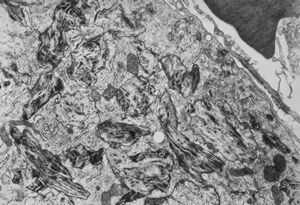

M,54y. | Whipple disease

Whipple disease